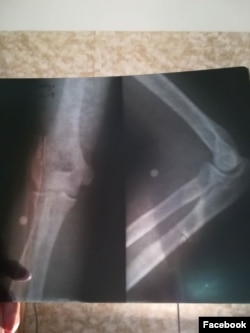

დაკარგული მხედველობა, სხეულში ჩარჩენილი ტყვიები და დაცხრილული ზურგები - რას ყვებიან დაშავებულები